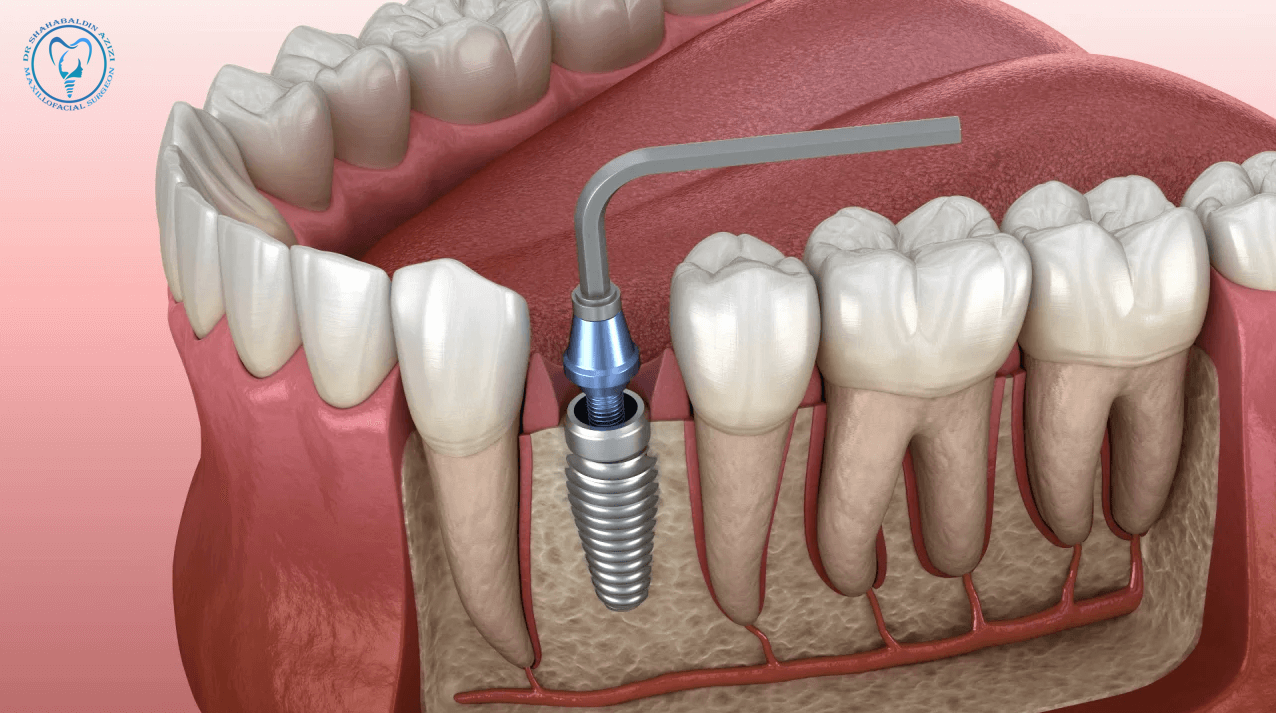

ایمپلنت نیازمند جراحی، بهبود استخوان، و سلامت عمومی مناسب است. بیماریهایی که سیستم ایمنی را تضعیف میکنند، فرآیند ترمیم را کند میکنند یا خونرسانی را دچار اختلال میسازند، ممکن است مانع موفقیت ایمپلنت شوند. بنابراین شناخت این بیماریها اهمیت زیادی دارد.

در بسیاری موارد، اگرچه ایمپلنت اولیه ممکن نیست، اما پس از درمان بیماری زمینهای یا استفاده از روشهای خاص مانند پیوند استخوان، ایمپلنت قابل انجام است. همچنین روشهایی مانند دندان مصنوعی، بریج یا مینی ایمپلنت میتوانند جایگزین مناسبی باشند.

ایمپلنت دندان یک راهحل بسیار مؤثر برای جایگزینی دندانهای از دسترفته است، اما برای همه افراد مناسب نیست. بررسی دقیق سوابق پزشکی، کنترل بیماریهای مزمن، و رعایت نکات بهداشتی و درمانی، کلید موفقیت ایمپلنت محسوب میشود. مشورت با پزشک متخصص و دندانپزشک مجرب، قبل از هر اقدامی ضروری است.